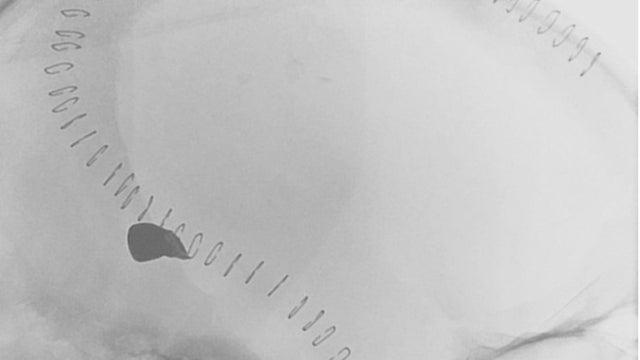

A bullet lodged in his brain

Fragments of the bullet remained in Smith's brain. His doctors say that to retrieve the bullet could risk causing further damage.